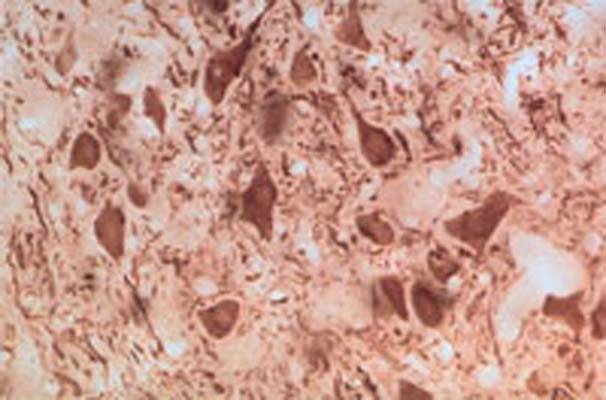

This antiserum stains trigeminal motor neurons in rat brain stem.